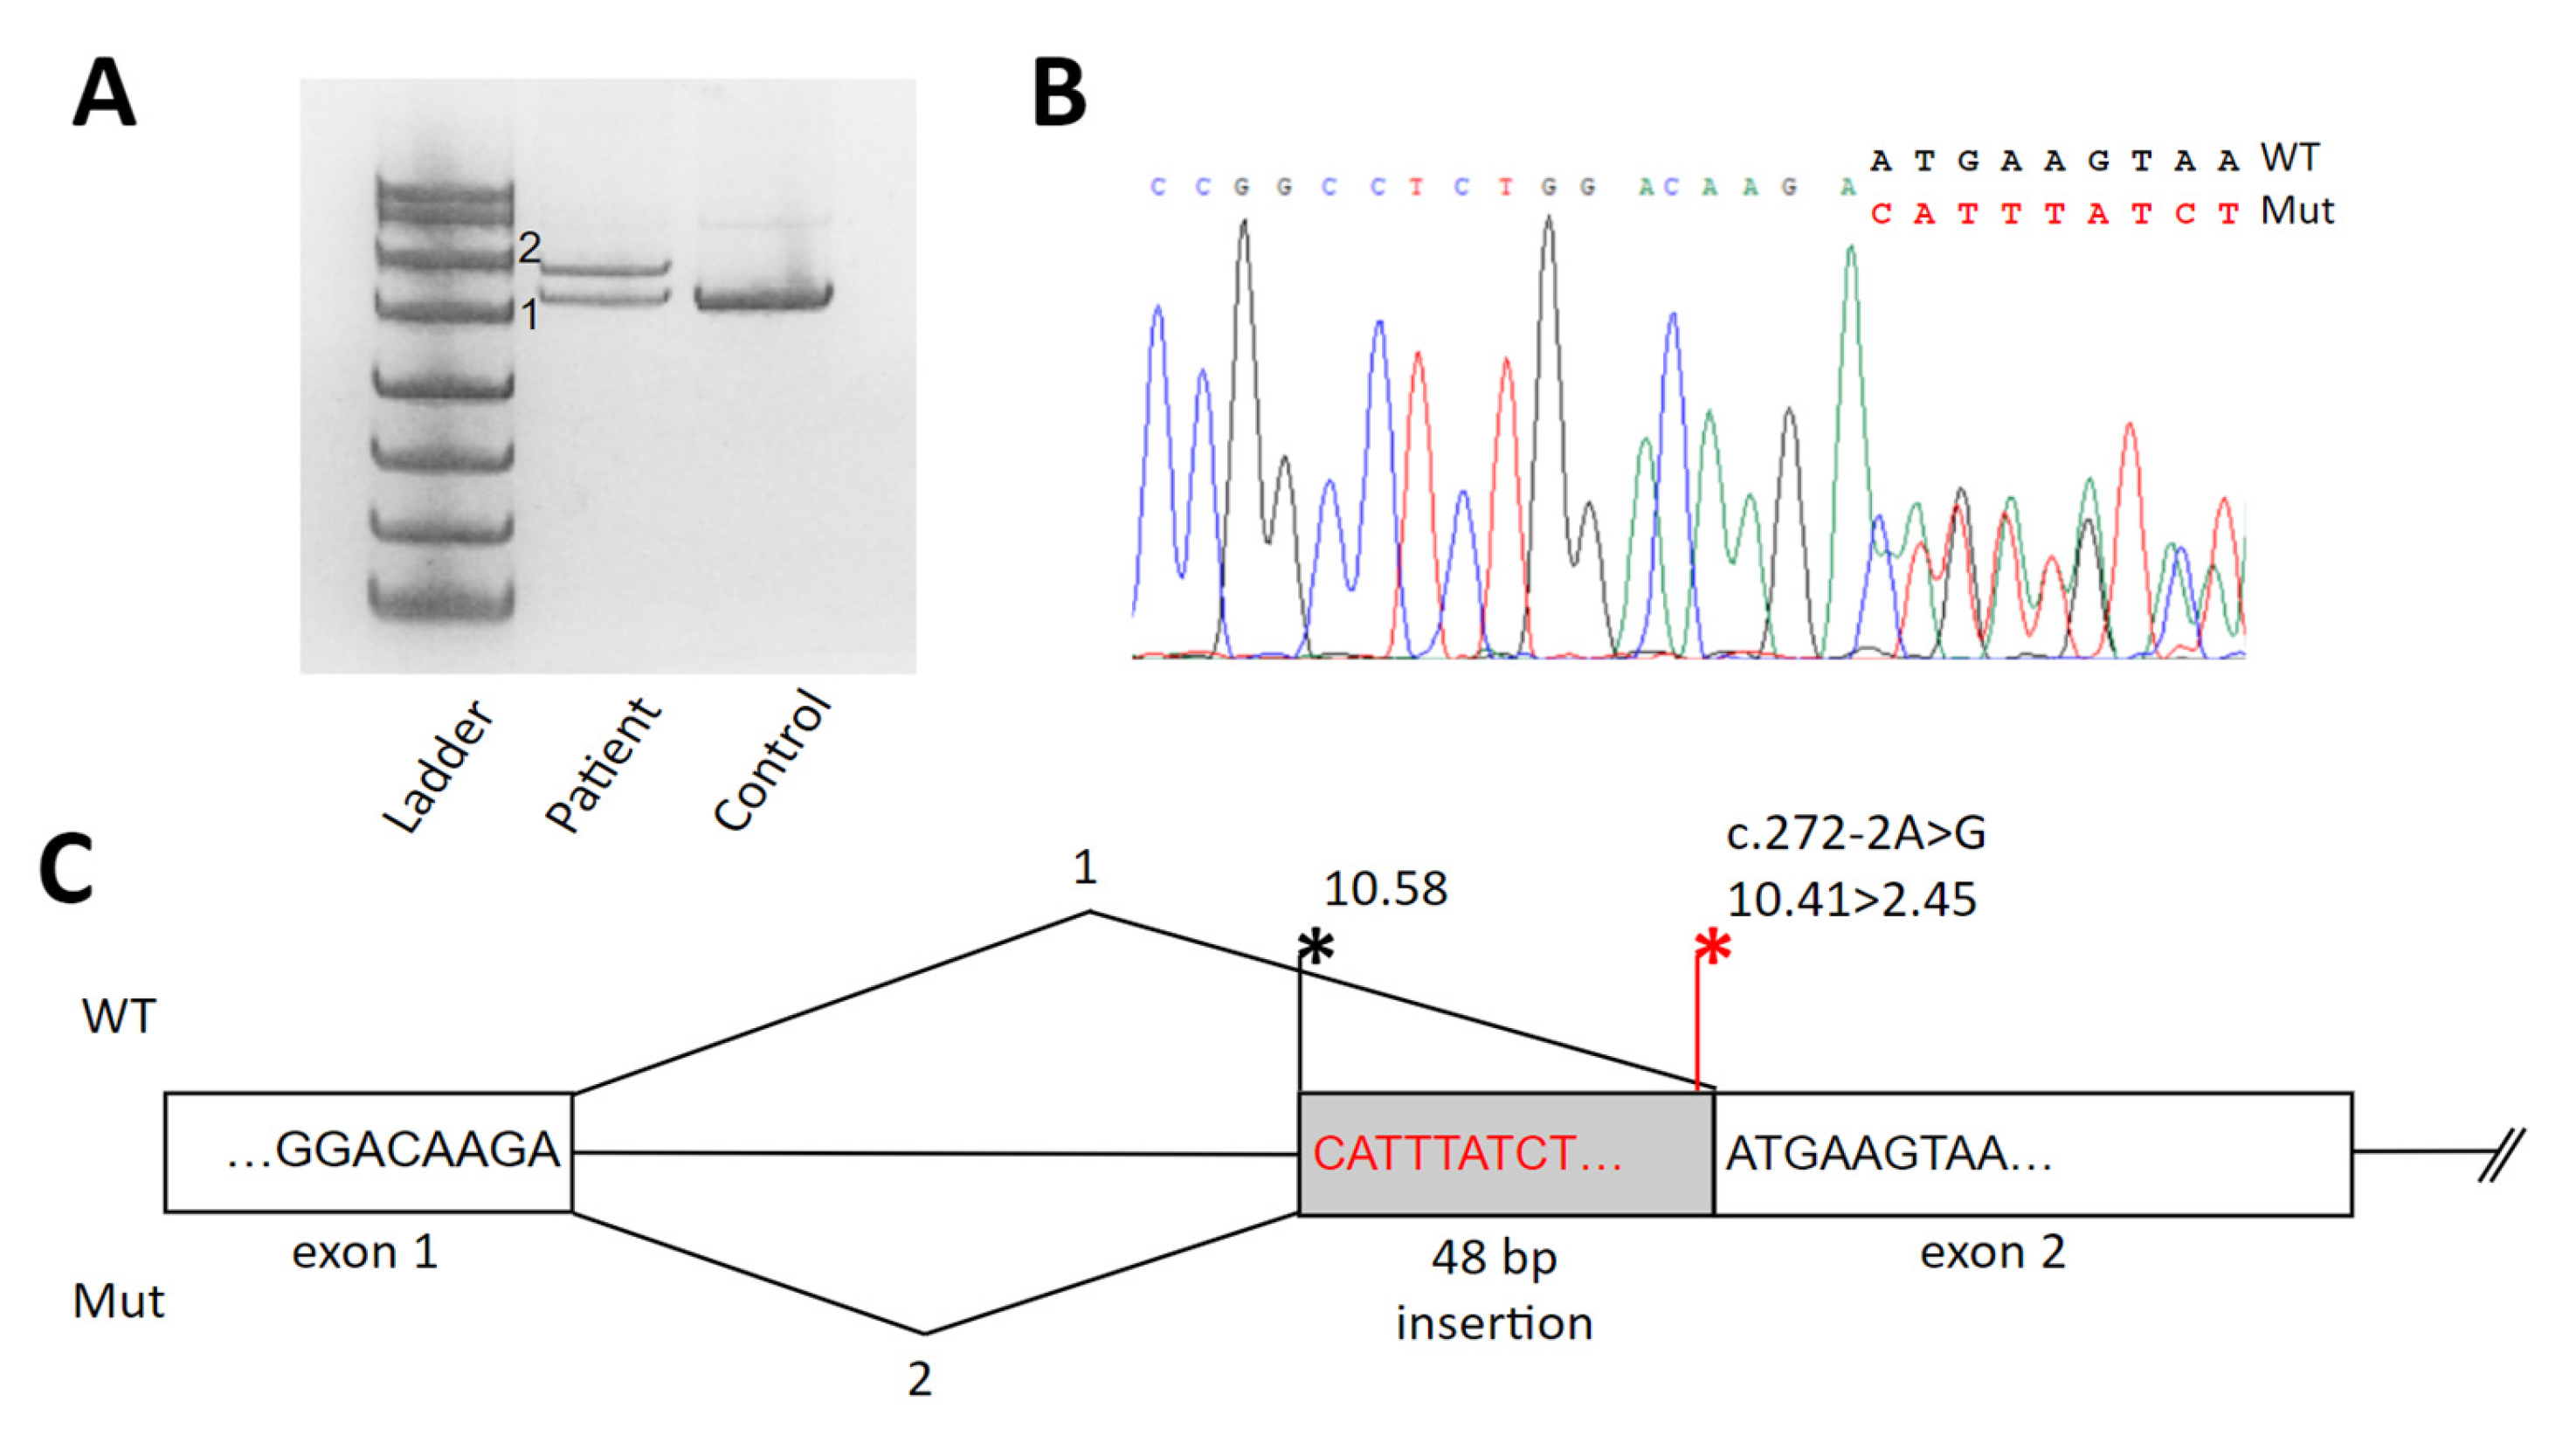

3.3. Molecular Findings

Massive Parallel Sequencing